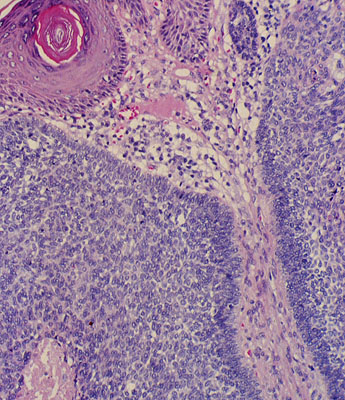

Basal cell

carcinoma

, micro,

invasive

mass of basaloid cells.